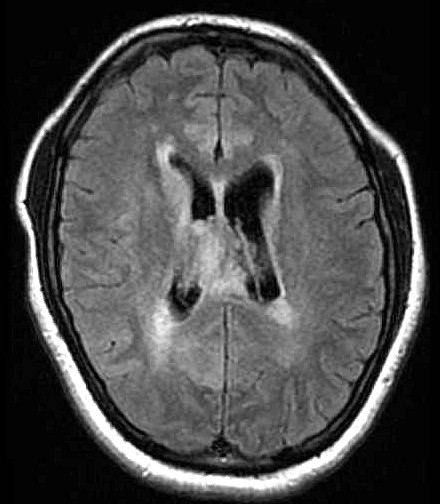

| Fem. 17a. |

| Nódulo sólido homogêneo preenchendo o III ventrículo, com limites precisos, com hipossinal em T1 e hipersinal em T2 e FLAIR, que se impregna por contraste paramagnético. Lesão menor implantada no assoalho do IV ventrículo provavelmente representa disseminação por via liquórica. |

| F. 17a. Tumor teratóide rabdóide atípico de III ventrículo. RM | HE | VIM, GFAP | HHF35, desmina, 1A4 | AE1AE3, EMA |